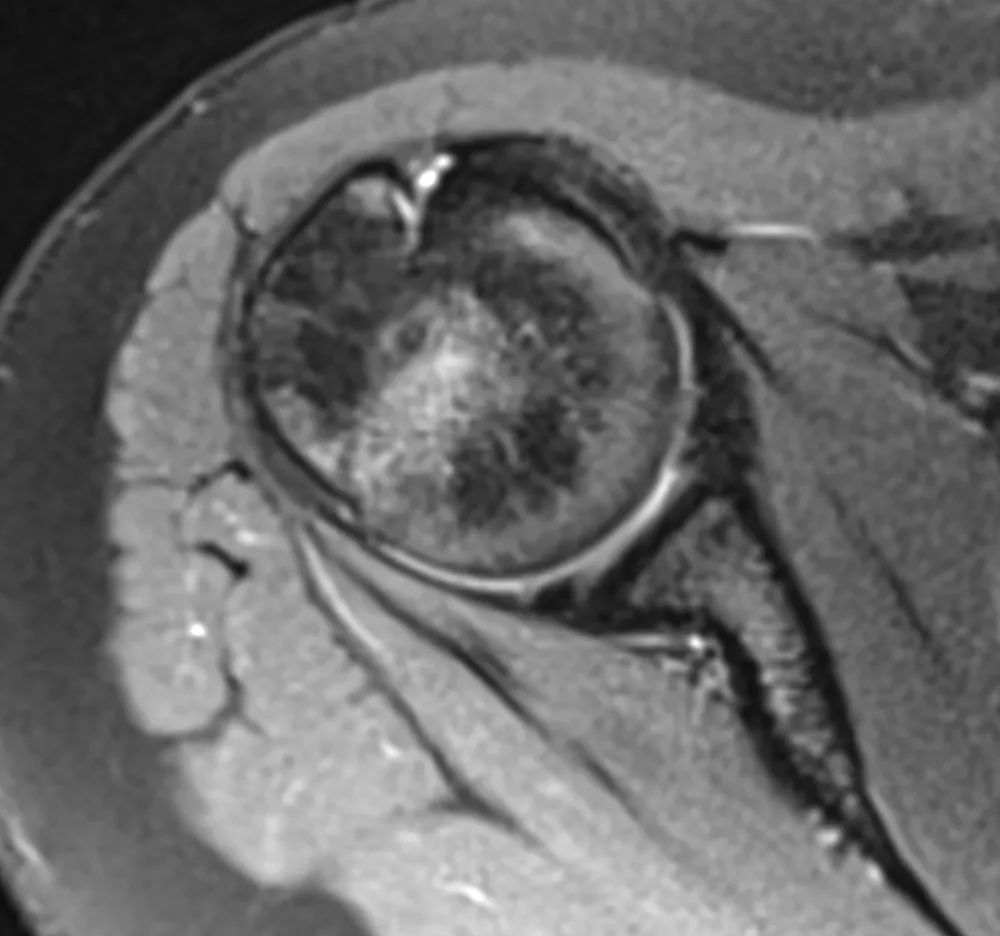

Junge und aktive Handballspielerin (15 Jahre) mit funktioneller dorsaler Schulterinstabilität (Abb. 1). Erstluxation beim Melden in der Schule. In der Folge konstante Subluxationen oder Luxationen der Schulter beim Anheben des Armes zwischen 60–80° Flexion. Hieraus resultierend konnte die Handballkarriere nicht fortgesetzt werden. Die sportlichen, aber auch die alltäglichen Einschränkungen führten darüber hinaus zu einer hohen psychischen Belastung. Bisherige Therapiemaßnahmen blieben frustran.